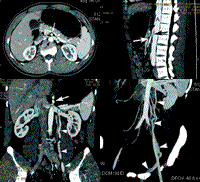

图1左肾静脉水平增强CT扫描,示肠系膜上动脉(白箭号)位于腹主动脉(黑箭号)正前侧,两者间距离仅2.5mm。左肾静脉左侧(白箭头)直径明显大于右侧(黑箭头),约为右侧的2.5~3倍

图2沿主动脉长轴的多平面重组像(MPR),示肠系膜上动脉(白箭号)与腹主动脉(A)间的夹角为13。。可见位于两者之间受压变窄的左肾静脉(黑箭号)

图3沿双侧肾静脉长轴的曲面MPR,示左肾静脉近侧增宽(LRV),经肠系膜上动脉与腹主动脉后受压变窄,汇入下腔静脉(IVC)。箭号示肠系膜上动脉的断面。箭头示曲张的左侧精索内静脉

图4厚块最大密度投影(Slab MIP),示曲张的左侧精索内静脉(箭头)汇入左肾静脉, 百拇医药